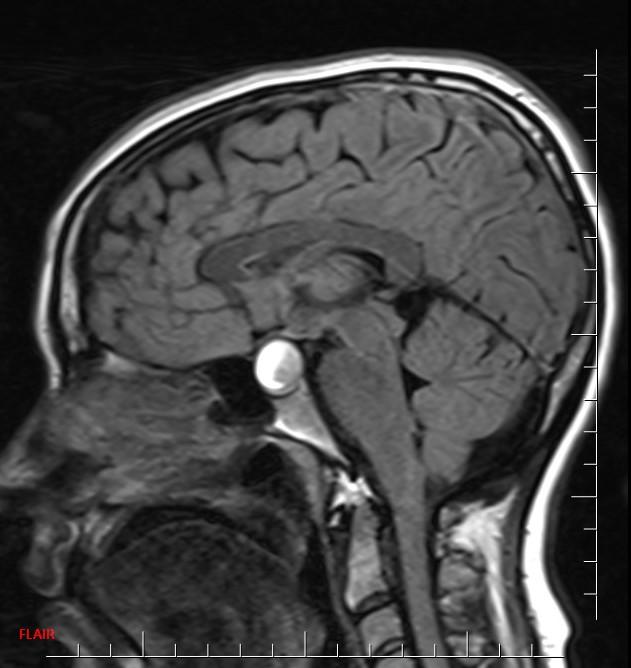

*30-year-old pregnant woman with headache and diplopia.

What is the most likely diagnosis?

Answer: Pituitary apoplexy

MR images reveal an ovoid lesion (red arrows) in the pituitary fossa with suprasellar extension. The optic chiasm is compressed (yellow arrows). The lesion is T1 and T2 hyperintense showing blood-blood fluid level (blue arrows).